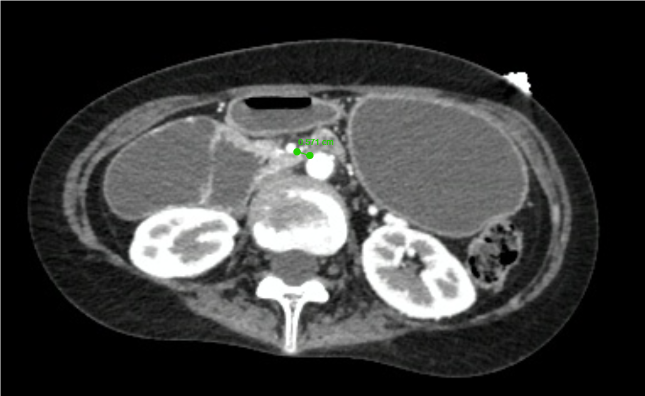

Ảnh chụp CT bụng của nữ bệnh nhân.

Kết quả thăm dò hình ảnh và chụp CT xác định bệnh nhân mắc hội chứng động mạch mạc treo tràng trên - một bệnh lý hiếm gặp. Trong trường hợp này, đoạn tá tràng bị chèn ép giữa hai mạch máu lớn trong ổ bụng, khiến thức ăn không thể lưu thông bình thường. Tình trạng tắc nghẽn kéo dài khiến bệnh nhân ăn uống kém, nôn ói liên tục, dẫn đến suy dinh dưỡng nặng, teo cơ toàn thân và suy mòn.